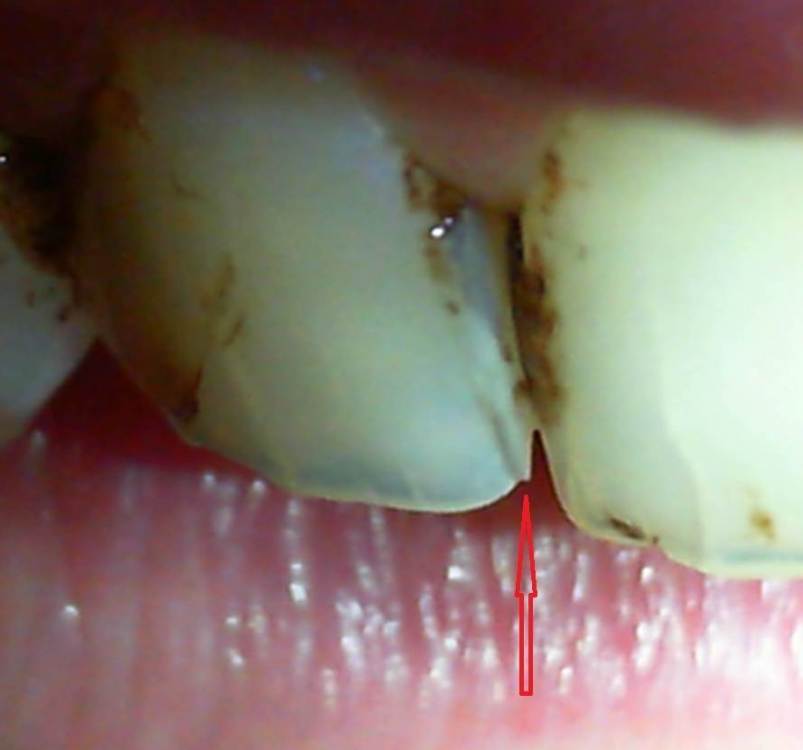

На 26-й день при умеренной жевательной нагрузке (решил покончить с зависимостью от чипсов и употребил четыре больших и одну среднюю банку Pringles - однако никакого жёсткого накусывания и никакого звука трескающегося зуба не происходило) - образовалась наклонная вертикальная трещина, заходящая на режущий край, что ощущается языком (фото 1-5). Удивительным образом, характер боли после этого практически не поменялся.

Я вспомнил, что врач после постановки пломбы с большим дёргающим усилием вытаскивал именно со стороны зуба №11 некий формирующий элемент. Скорее всего, это была не т.н. матрица, а нечто предыдущего поколения, вроде металлической пластины.

Отмечу также, что пломба имеет нависающий край, о который разволокняется зубная нить, и некий карман, куда попадают остатки пищи.  Читал, что нависающий край пломбы образуется, когда врач не использует матрицу и матрицедержатель, а использует металлическую пластину. Также сама пришеечная часть ощущается "заострённой", нежели округлой.